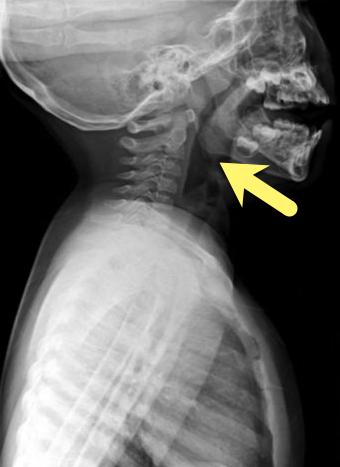

Diagnosis: Fishbone lodged in oropharynx

- A patient's presentation is typically as above, well appearing with a feeling of something being stuck after eating a meal.

- Plain films are typical the initial imaging choice (sensitivity around 35%) while CT has a sensitivity of 95% for bones

- Plain films have lower sensitivity for organic matter, if available ultrasound can be used.